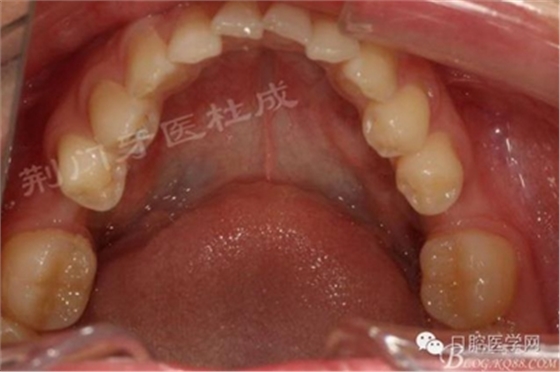

術(shù)前口內(nèi)照片:

檢查:16齲壞穿髓,探(-)叩(+++),無松動(dòng),36 46 缺失,37 47 近中傾斜嚴(yán)重,44畸形中央尖牙體變色,叩(+),溫度測(cè)試無反應(yīng) ,18 28 38 48 萌出牙體偏頰